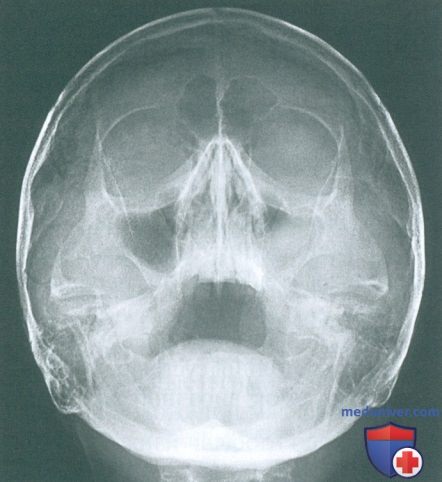

Рентгенография небного шва: Медицинские исследования и диагностика